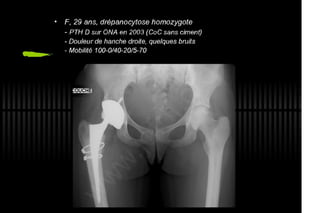

2013 032. Douleur sur PTH céramique-céramique

032. Douleur sur PTH céramique-céramique - Painfull THA with Alumine-Alumine bearing